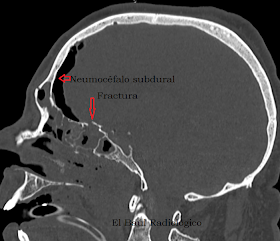

FIGURA 1M) Reconstrucción MPR de orientación Sagital. En ella se aprecia la fractura en la base del cráneo (flecha roja) y la ocupación hemorrágica de las celdillas etmoidales y los senos frontal y esfenoidal.